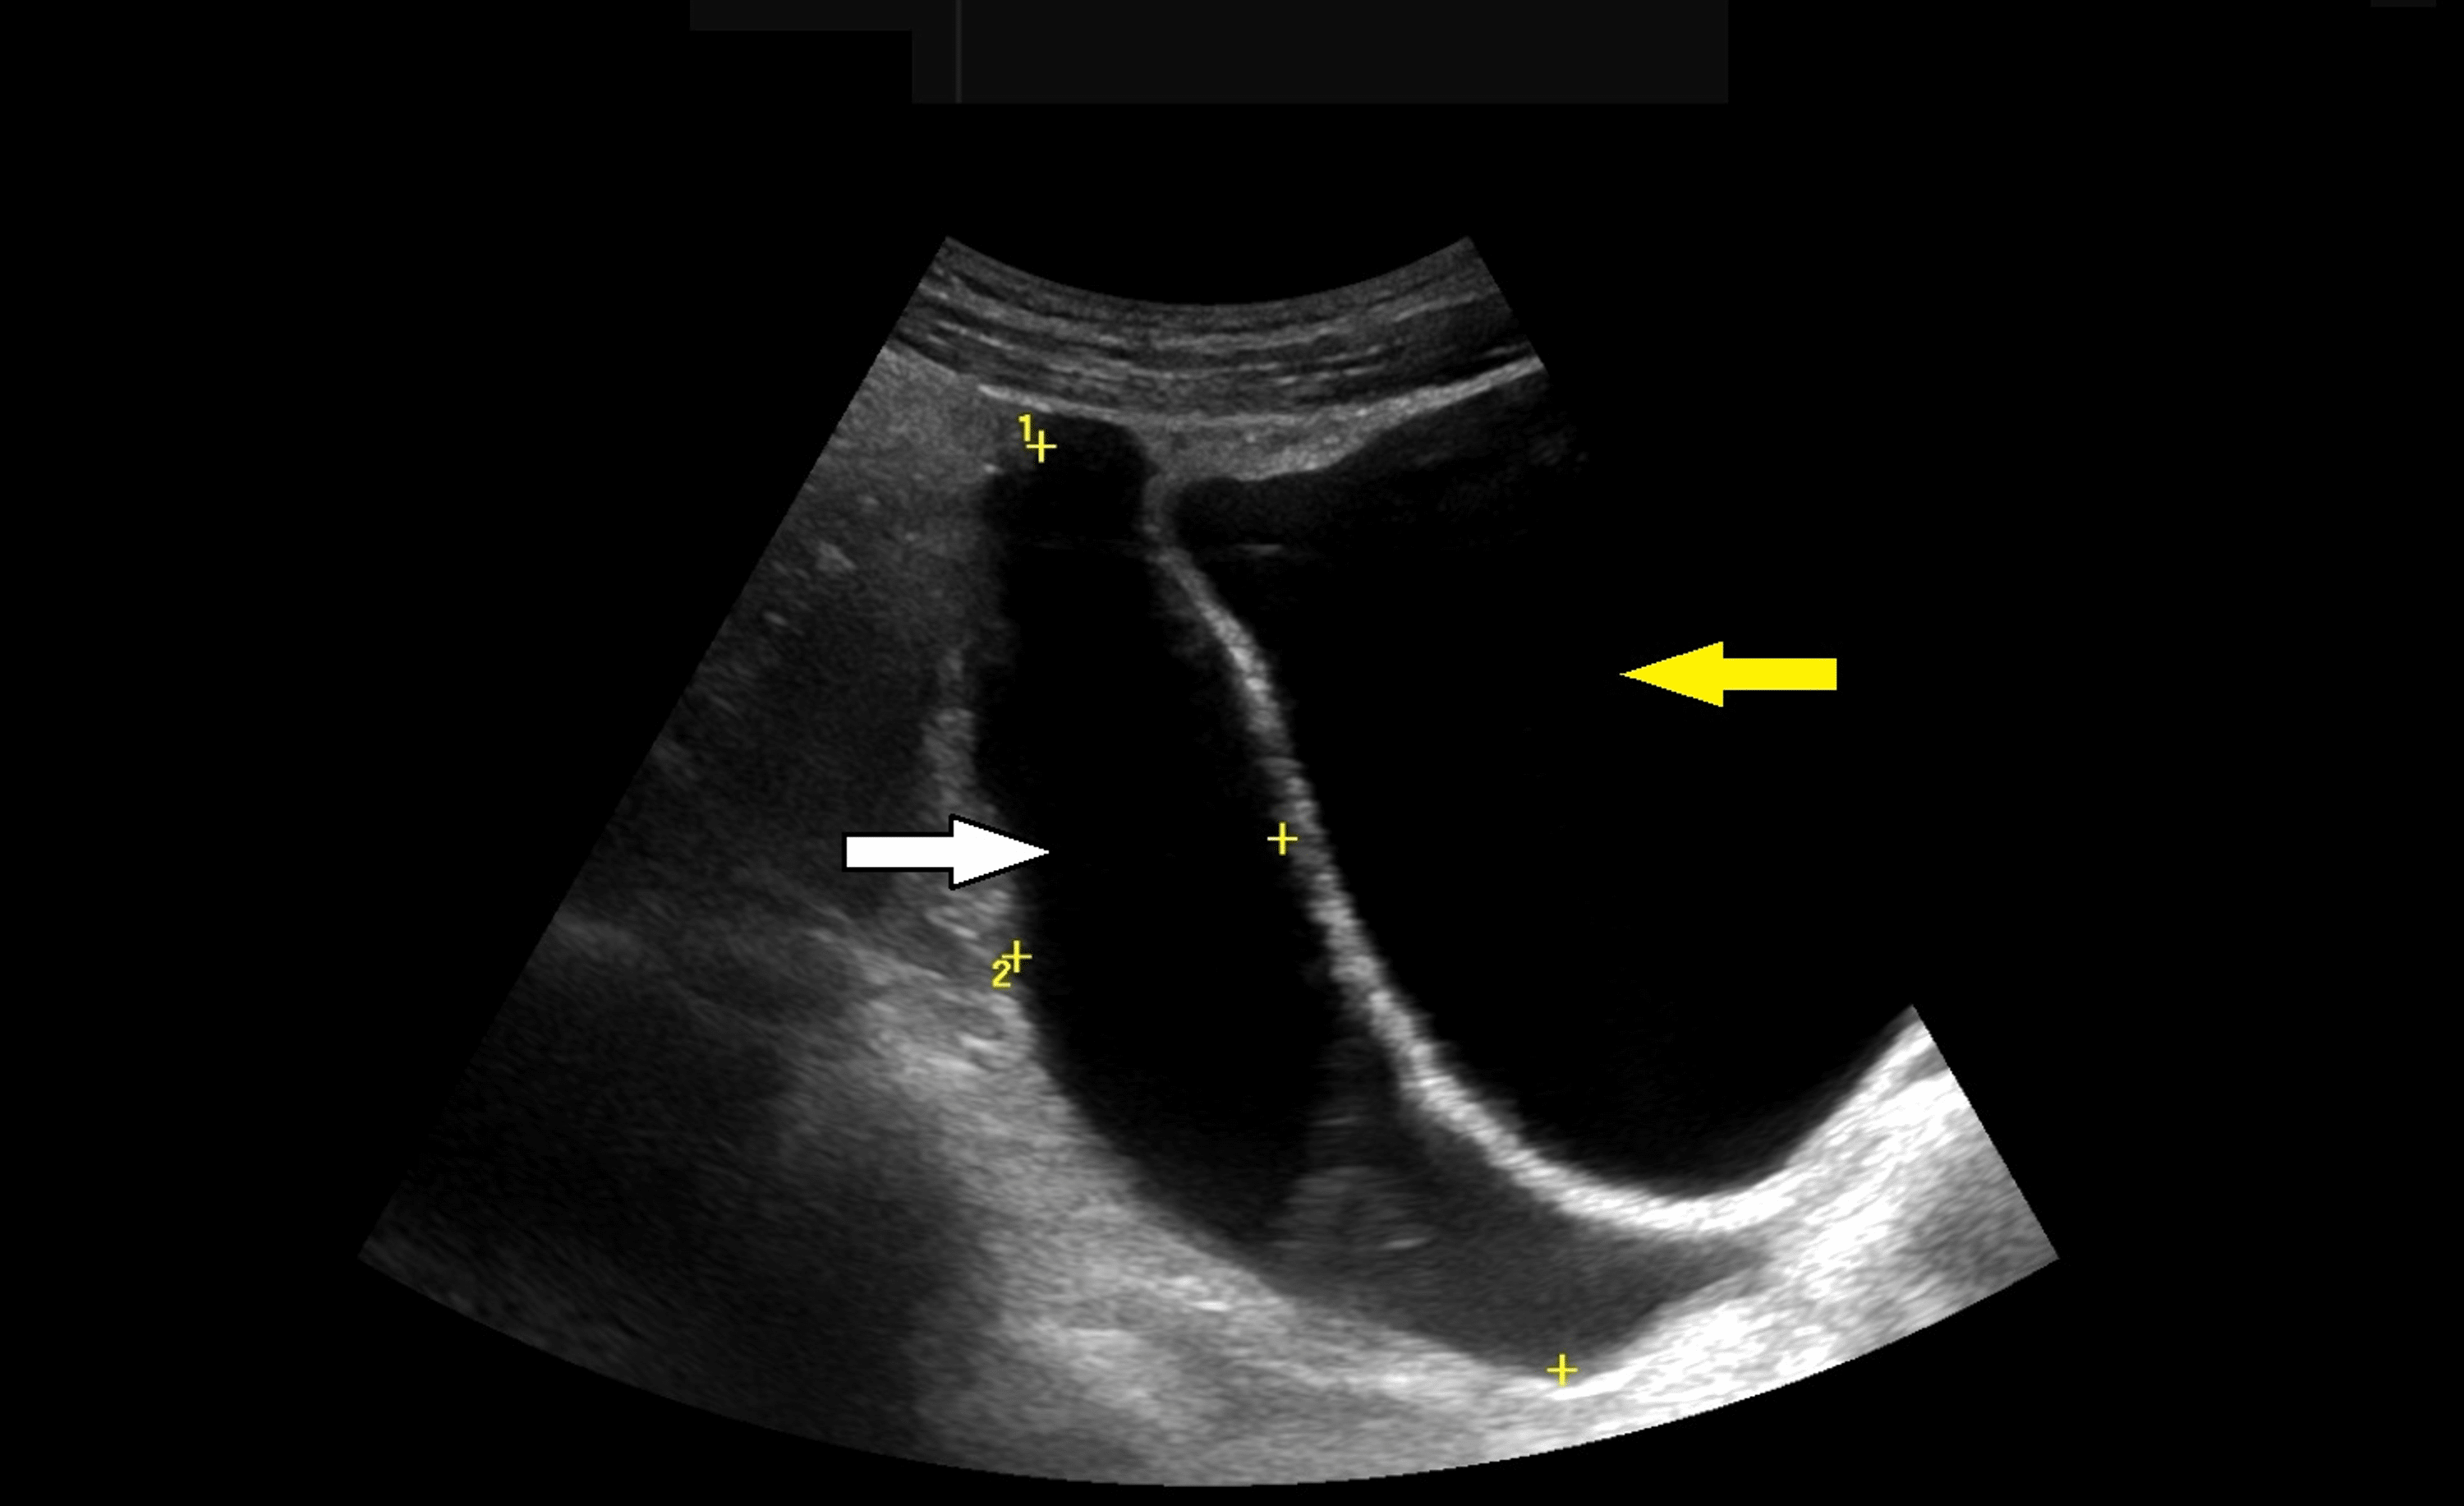

Pelvic ultrasound A and B showing median and right paramedian

Pelvic ultrasound A and B showing median and right paramedian What Does Yellow Mean On A Pelvic Ultrasound Yellow/orange are not usual doppler colors. Yellow is not a primary color in doppler imaging, but it often appears at the interface between red and blue. Color on ultrasound monitor screen represents movement, mostly due to blood vessels but not always. This yellow hue indicates turbulence or. A quick and effective way to detect and diagnose pelvic inflammatory disease in. What Does Yellow Mean On A Pelvic Ultrasound.